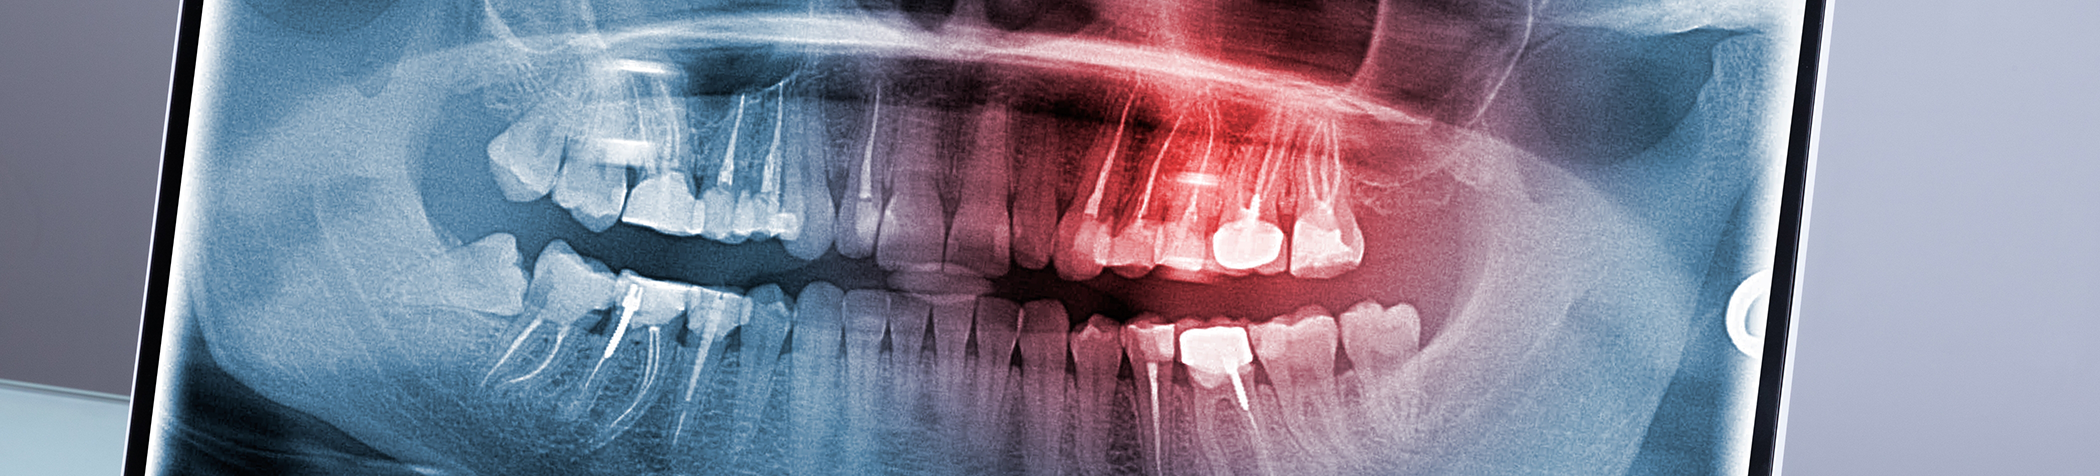

Digital X-Rays

Children and adults can expect safer dental experiences thanks to our updated Clio digital X-ray sensors. Not only do they require less radiation than traditional radiographs, but this imaging system leads to a faster overall experience thanks to the immediate images that are captured. In seconds, patients and our dentists can see what lies beneath the surface of one’s smile, making it easier to identify problem areas during an appointment.